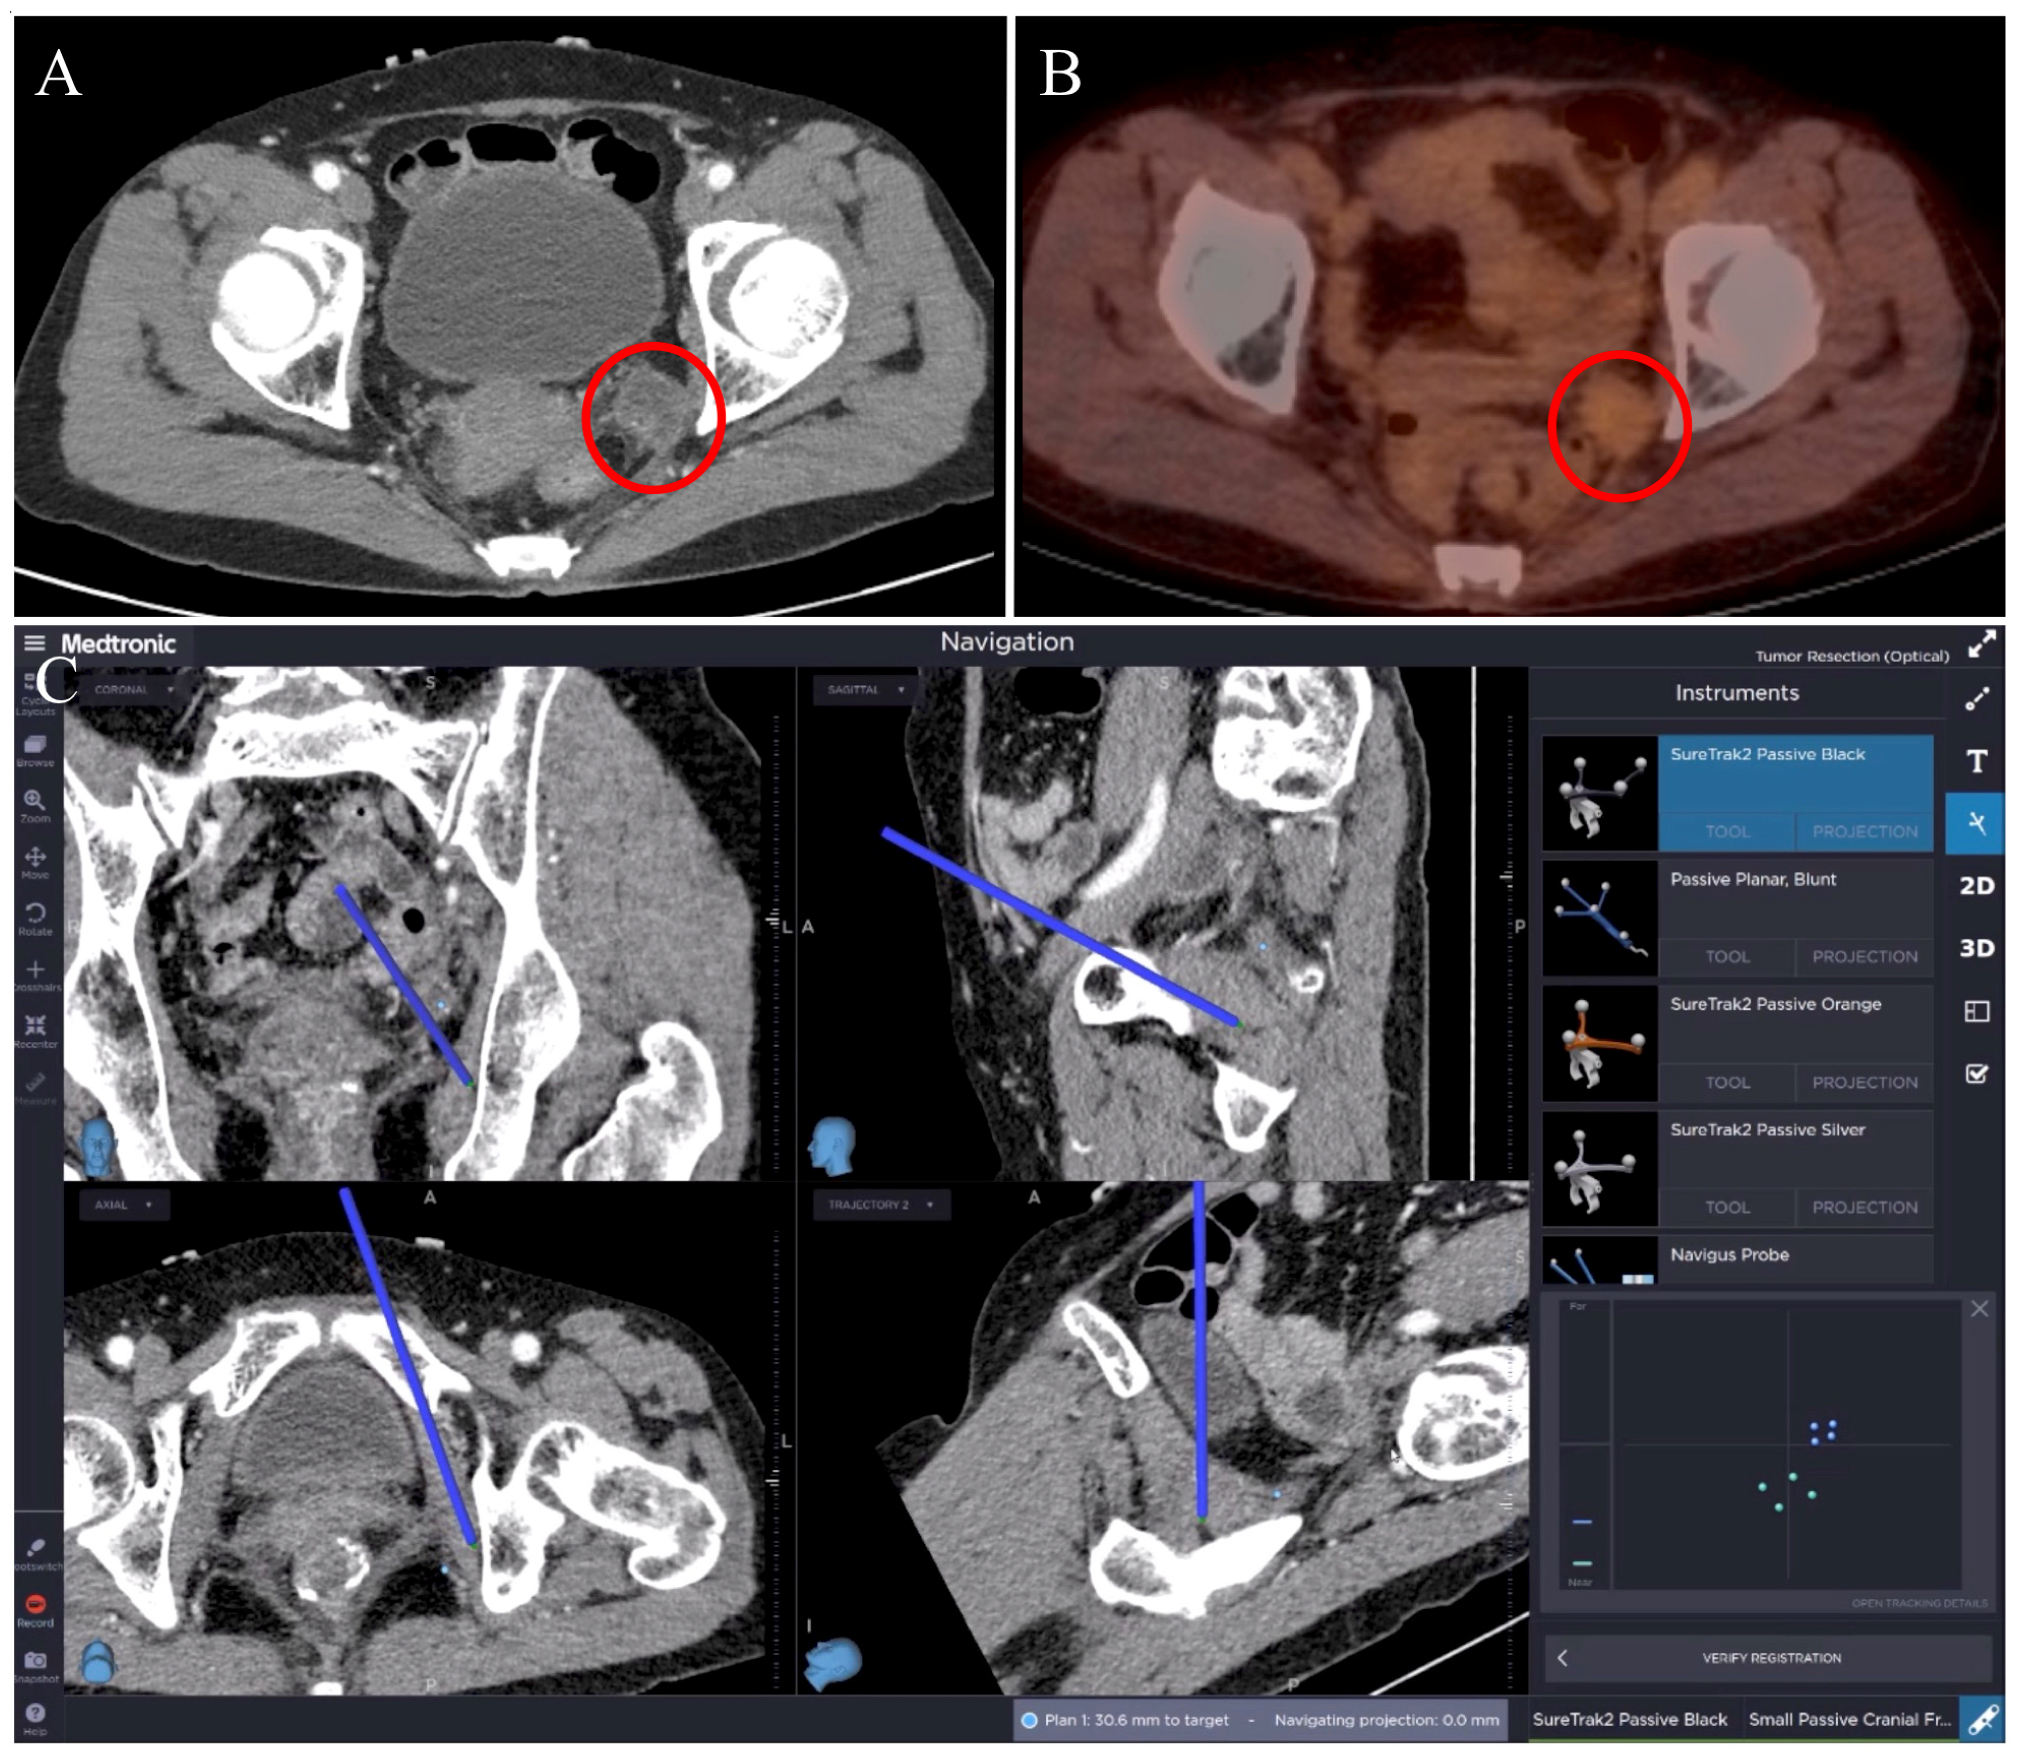

3.2. Case 2: Rectal Cancer Local Recurrence